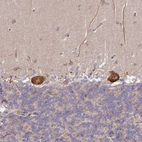

Immunohistochemical staining of human placenta shows weak to moderate cytoplasmic positivity in trophoblastic cells.